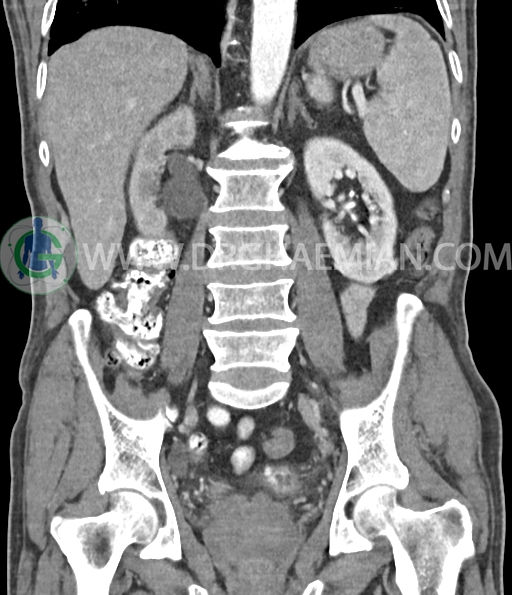

در سی تی اسکن اسپیرال شکم و لگن با و بدون کنتراست خوراکی و وریدی (مولتی دیدکتور 16 با مقاطع ظریف و بازسازی های ساژیتال و کرونال) :

کیست کورتیکال به قطر 15mm در پل تحتانی کلیه چپ دیده می شود.

افزایش ضخامت جداری و نامنظمی و لوبولاسیون همراه باenhancement مطرح کننده انفیلتراسیون و ضایعات تومورال در سمت راست ناحیه ترایگون و دیواره لترال راست مثانه دیده می شود که باعث اتساع حالب راست و هیدرونفروز moderate در کلیه راست شده است . این یافته های می توانند مطرح کننده TCC باشند .fat stranding در اطراف مثانه مشهود است. بیرون زدگی توده مانند به قطر 18mm در سمت راست ناحیه ترایگون دیده می شود که می تواند مطرح کننده گسترش اکسترا وزیکولر تومور باشد . لنفادنوپاتی با SAD=10mm درlevel ایلیاک داخلی چپ رویت شد . لنف نود دیگر با SAD= 5mm در همین ناحیه مشهود است. با توجه به این یافته ها stage احتمالی تومور T3، N1 or N2 می باشد .